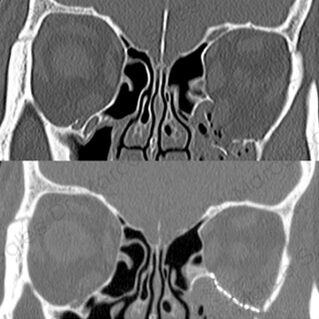

ÓRBITA

TUMORES ORBITARIOS